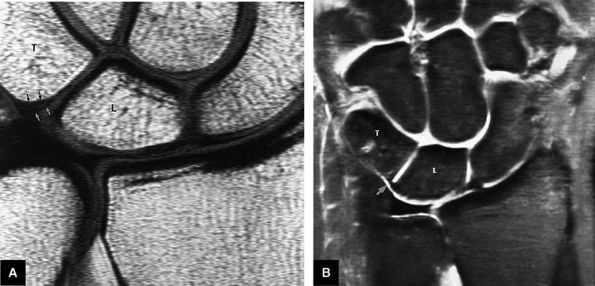

FIGURE 10.2 ● Optimized signal-to-noise in routine wrist imaging using a four-channel phased-array wrist coil on a 3T imager. (A) Coronal PD FSE image. (B) Coronal FS PD FSE image. (C) Axial PD FSE image.